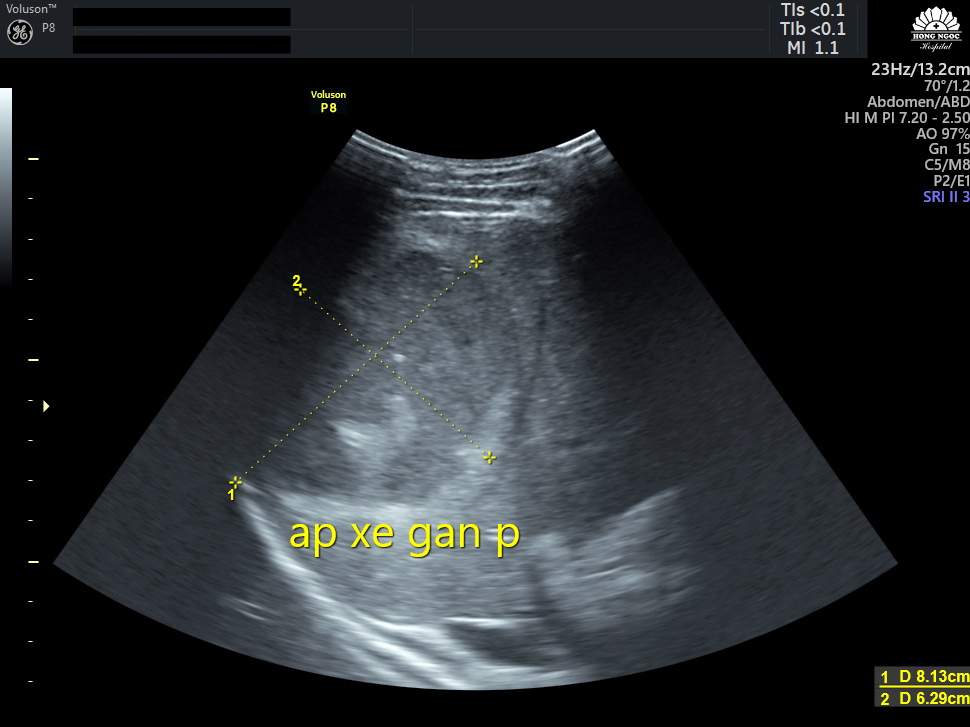

Kết quả siêu âm và chụp cắt lớp ổ bụng của anh T cho thấy nhu mô gan phải có xuất hiện khối áp-xe lớn với kích thước 8.13x6.29cm, dịch không trong, có nhiều vách, khối tổn thương nằm sát bao gan và màng phổi.

Khối áp-xe lớn với kích thước 8.13x6.29cm, nằm sát bao gan và màng phổi Khối áp-xe lớn với kích thước 8.13x6.29cm, nằm sát bao gan và màng phổi